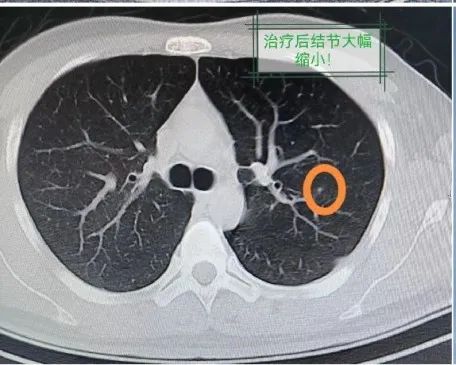

近日,上海市第十人民医院中西医整合医学科就收治了一名26岁年轻小伙,因反复咳嗽、痰中带血块,CT检查显示左肺上叶有一枚直径达12毫米的结节,周边伴圆环状磨玻璃影。

究竟是之前的病毒感染没好透,还是又出现了其他的问题?放不下心的他上医院检查,结果如当头一棒——左肺上叶发现一枚孤立结节,直径达到12毫米,且周边伴有圆环状的磨玻璃影,看起来就像雾霭天太阳周围的光晕一般。

病因明确,治疗就能有的放矢。遵医嘱口服抗真菌药氟康唑一个多月,同时密切监测肝肾功能(抗真菌药常有肝肾损伤等副作用),其肺部的病灶基本消失。